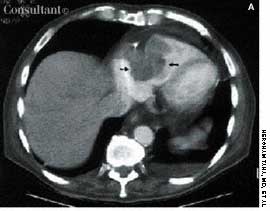

A 56-year-old man who had hematuria for 2 weeks underwent ultrasonography. This disclosed a well-circumscribed cyst in the lower pole of the left kidney and echogenic foci in the upper pole of the right kidney, without any evidence of posterior shadowing. A hyperechoic, well-circumscribed, circular focus was also seen in the right lobe of the liver. Abdominal CT confirmed the presence of a left renal cyst and revealed a 4.7-cm hypodense lesion in the right lobe of the liver, which suggested hemangioma.